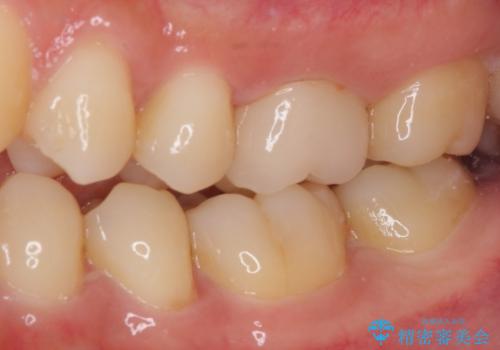

処置開始前から神経組織を部分的に除去する可能性が高いことが分かっていたため、ラバーダムなどの環境を整え、無菌的環境下にて処置を進めて行きました。

虫歯は深くまで進行しており、歯冠部の神経から出血が認められました。神経を部分的に除去したところ出血が治まったので、生体親和性の非常に高いセメントにて充填し、仮封をしました。

後日状態を確認したところ、残された神経に異常がなかったため、セラミッククラウンにて補綴治療を行いました。